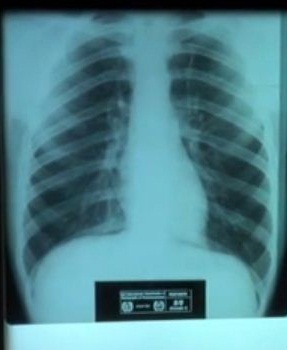

X-ray of healthy lungs

X-ray of healthy lungs.

OSHA has announced a proposed rule aimed at curbing lung cancer, silicosis, chronic obstructive pulmonary disease and kidney disease in America's workers. The agency currently enforces 40-year-old permissible exposure limits (PELs) for crystalline silica in general industry, construction and shipyards that are outdated, inconsistent between industries and do not adequately protect worker health. The proposed rule brings protections into the 21st century.